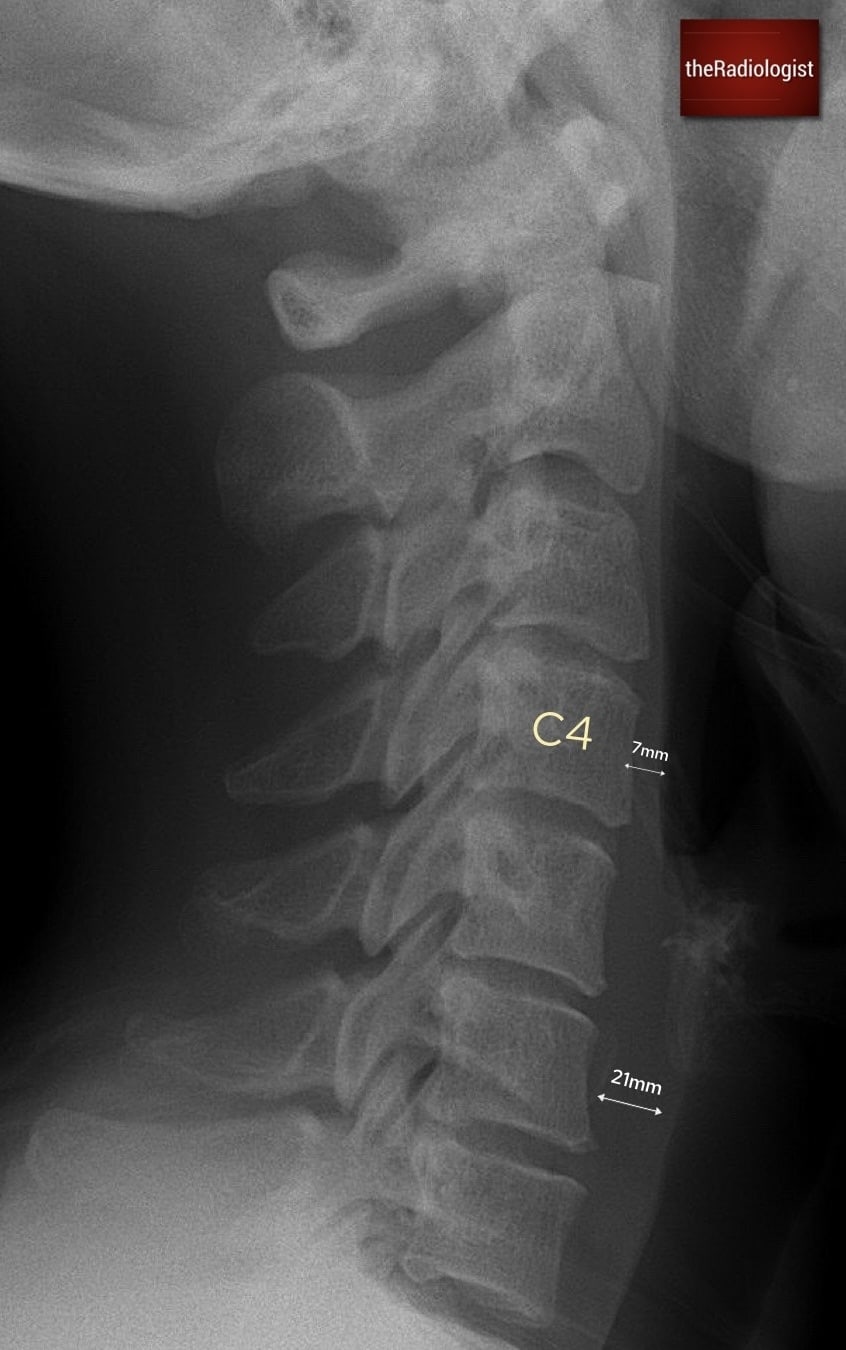

2. Prevertebral soft tissues

Next, assess the prevertebral soft tissues. These lie anterior to the vertebral bodies and can expand in response to haematoma, oedema, or soft tissue injury from an underlying fracture or dislocation. The accepted limits are up to 7 mm anterior to C1–C4 and up to 21 mm anterior to C5–C7. Any swelling beyond these values is suspicious for an acute injury and warrants closer scrutiny of the underlying vertebrae.

7 mm is the maximum prevertebral soft tissue thickness from C1-C4 whilst between C5-7 the maximal thickness is 21 mm

A simple rule to remember the key measurements on a lateral cervical spine X-ray is

3 × 7 = 21

3 mm: the maximum predental space in adults.

7 mm: the maximum prevertebral soft tissue thickness from C1–C4.

21 mm: the maximum prevertebral soft tissue thickness from C5–C7.